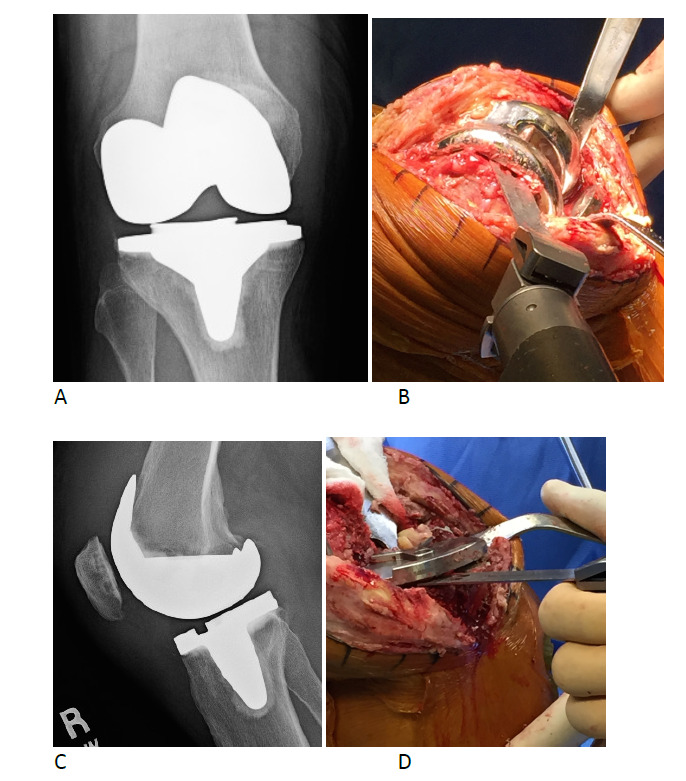

During the first stage procedure, the modular and customized knee spacer was implanted onto the clean bone surfaces using high viscosity gentamicin-loaded bone cement (see Figures 1 and 2). Trialing with flexion-extension matching was done prior to spacer placement to confirm the optimum spacer thickness and provide a smooth knee range of motion (see Figure 3) and reconstitute the flexion/extension gap. Cement in doughy form was layered on the undersides of the femoral and tibial components to make the spacer easier to remove during the second stage procedure. Inpatient physiotherapy was started immediately with knee range of motion and quadriceps strengthening exercises as soon as the pain permitted and full weight bearing ambulation with a walker was performed on the first post-operative day. Patients were discharged home or to a sub-acute nursing facility when medically stable with intravenous antibiotics monitored by an infectious disease specialist. The patients were followed up regularly. Post-first stage procedure intravenous antibiotics were started as per culture and sensitivity report of the fluid and tissue sent for culture preoperatively or intraoperatively. Antibiotics were continued for 6-8 weeks followed by a 4-week antibiotic free period.

_infected_total_knee_replacement_(ap_knee_x-ray)__(b)_femoral_exposure_and_component_re.png)